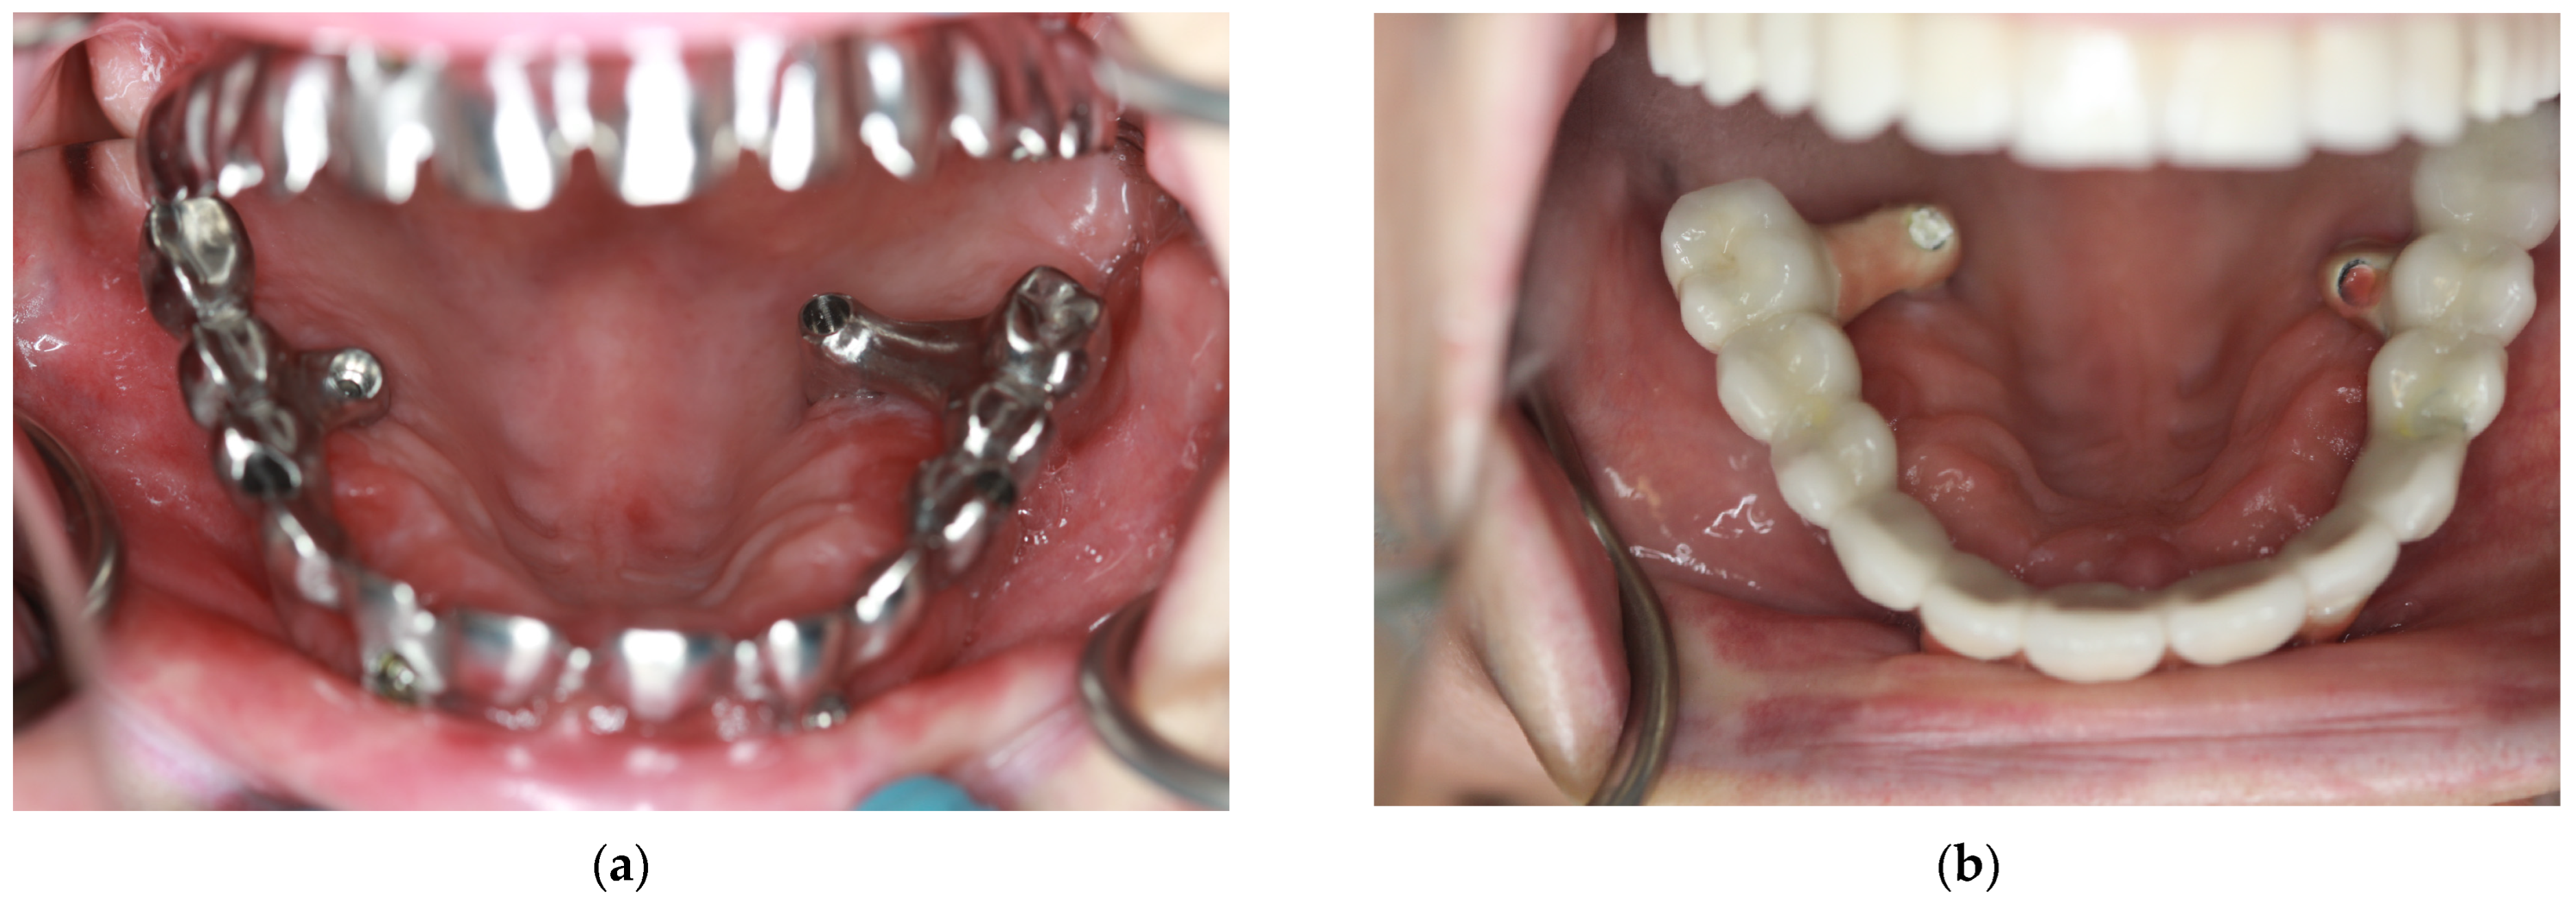

2. Materials and Methods

2.2. Surgery